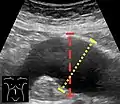

Aortic measurement on abdominal ultrasonography in the axial plane between the outer margins of the aortic wall.[33]

Ultrasonography in the sagittal plane, showing axial plane measure (dashed red line), as well as maximal diameter (dotted yellow line) which is preferred.